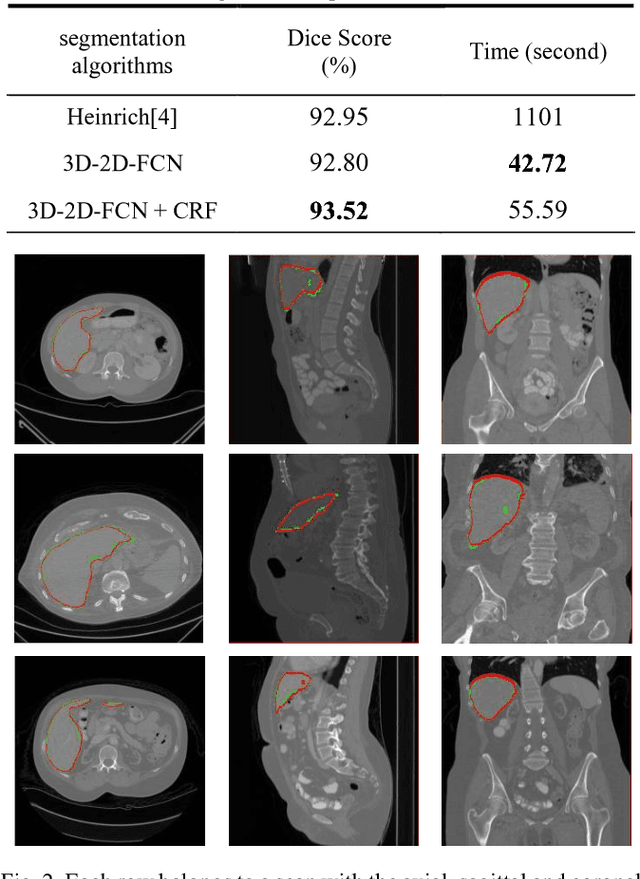

Abstract:The need for CT scan analysis is growing for pre-diagnosis and therapy of abdominal organs. Automatic organ segmentation of abdominal CT scan can help radiologists analyze the scans faster and segment organ images with fewer errors. However, existing methods are not efficient enough to perform the segmentation process for victims of accidents and emergencies situations. In this paper we propose an efficient liver segmentation with our 3D to 2D fully connected network (3D-2D-FCN). The segmented mask is enhanced by means of conditional random field on the organ's border. Consequently, we segment a target liver in less than a minute with Dice score of 93.52.